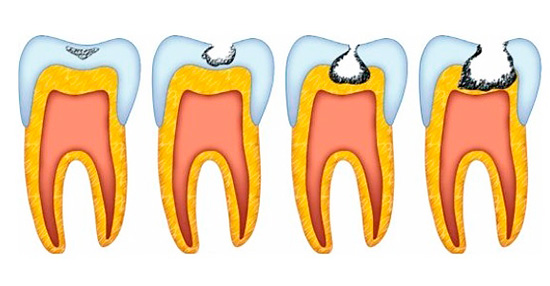

Data l'attuale classificazione delle lesioni cariose secondo l'OMS (Organizzazione mondiale della sanità), si distinguono i seguenti tipi di carie:

- Smalto Carie;

- Carie di dentina;

- Carie di cemento.

su fase iniziale della carie Questo processo di demineralizzazione avviene solo all'interno dello strato di smalto del sottosuolo. Di conseguenza, a seguito della lisciviazione attiva dei minerali e del loro lento ritorno, si forma un punto cariato. Può essere bianco o pigmentato a causa della colorazione dei "vuoti" dello smalto con coloranti e bevande.

Tuttavia, se si osserva lo stadio del danno allo smalto nelle prime fasi, si verifica un processo già irreversibile: la carie della dentina. In questa fase, i componenti minerali vengono già lavati dalla dentina stessa, che, come ricorderete, è la base del dente.